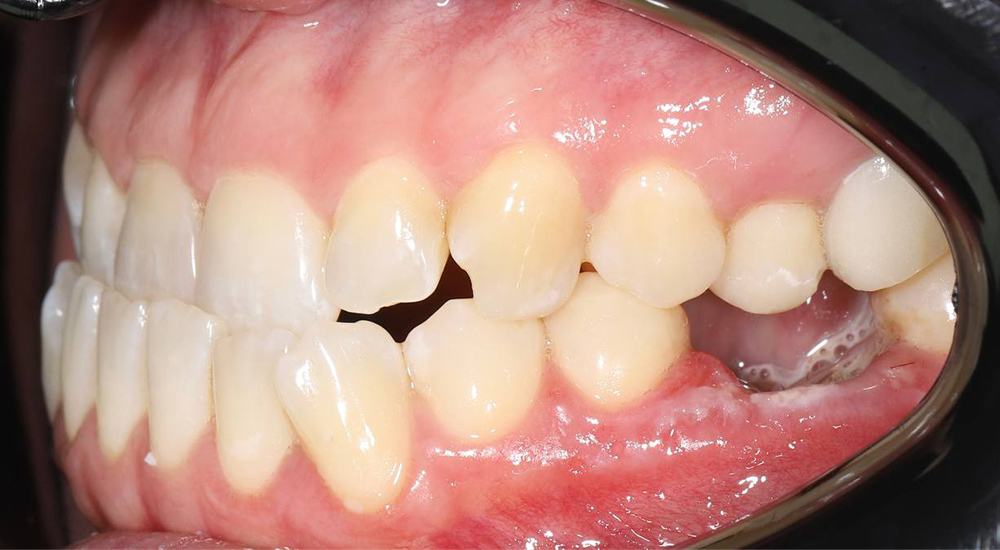

Коррекция прикуса и выравнивание зубов в подростковом возрасте